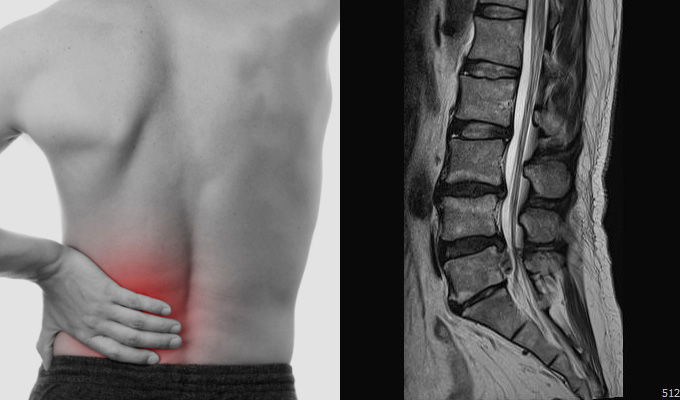

허리디스크의 대표적인 허리 통증입니다. 허리 통증은 갑자기 발생하거나 서서히 나타날 수 있으며, 통증이 심해지면 다리로 뻗쳐 내려가는 방사통을 동반할 수 있습니다. 또한 허리디스크는 마비, 감각 이상, 배뇨 장애 등의 증상을 유발할 수 있습니다.

1. 허리 통증

허리 디스크의 주요 증상 중 하나는 허리 통증입니다. 이 통증은 영향을 받은 디스크 부위에서 발생하며 둔한 통증, 날카로운 통증 또는 지속적인 불편감으로 나타날 수 있습니다.

통증의 강도는 다양할 수 있으며 영향을 받은 디스크에 압력을 가하는 움직임으로 악화될 수 있습니다.